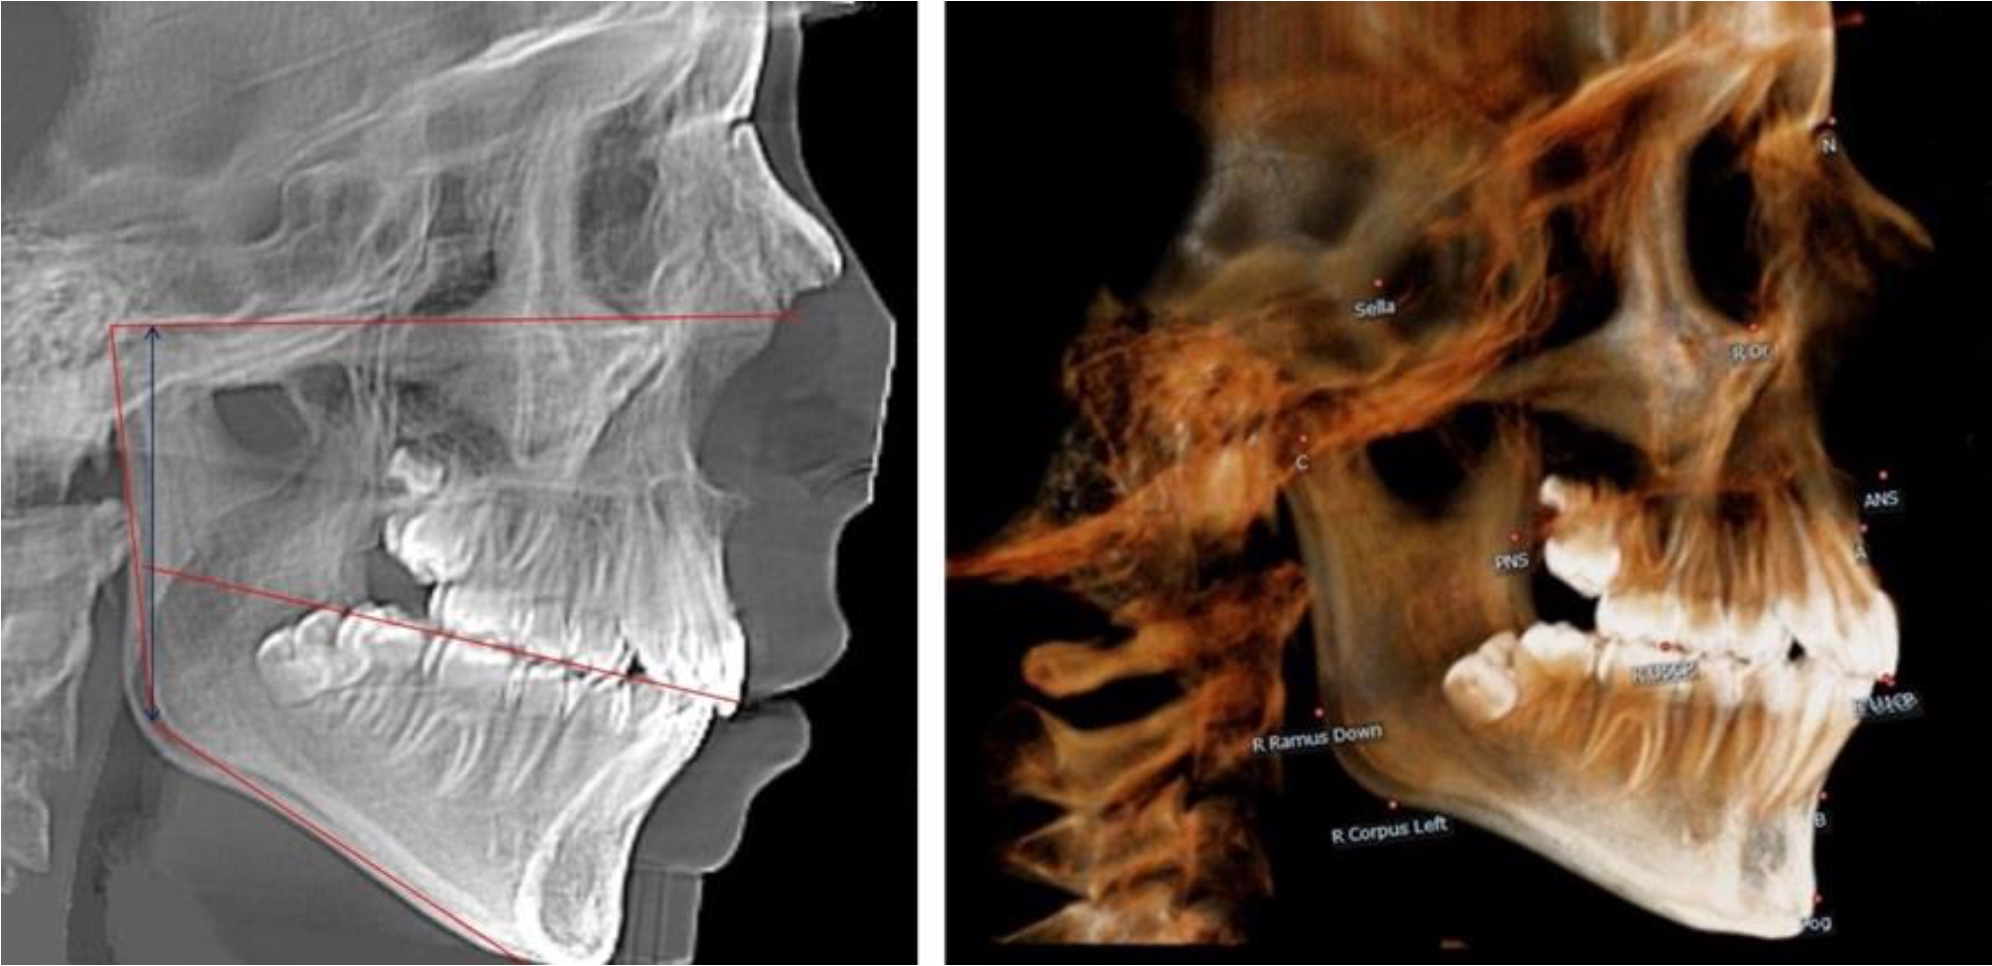

В 1-й группе были проанализированы 7 телерентгенограмм и 7 ортопантомограмм, что составило (6,60 ± 2,41) % от числа изученных рентгенограмм. На всех парах рентгенограмм угол нижней челюсти, измеренный на телерентгенограмме, соответствовал углу, полученному при построении угла на ортопантомограмме. Окклюзионная линия практически однотипно делила ветвь на два отдела (рис. 1).

Рис. 1. ТРГ и ОПТГ пациента 1-й группы

Рис. 2. ТРГ и ОПТГ пациента после прорезывания первых постоянных моляров